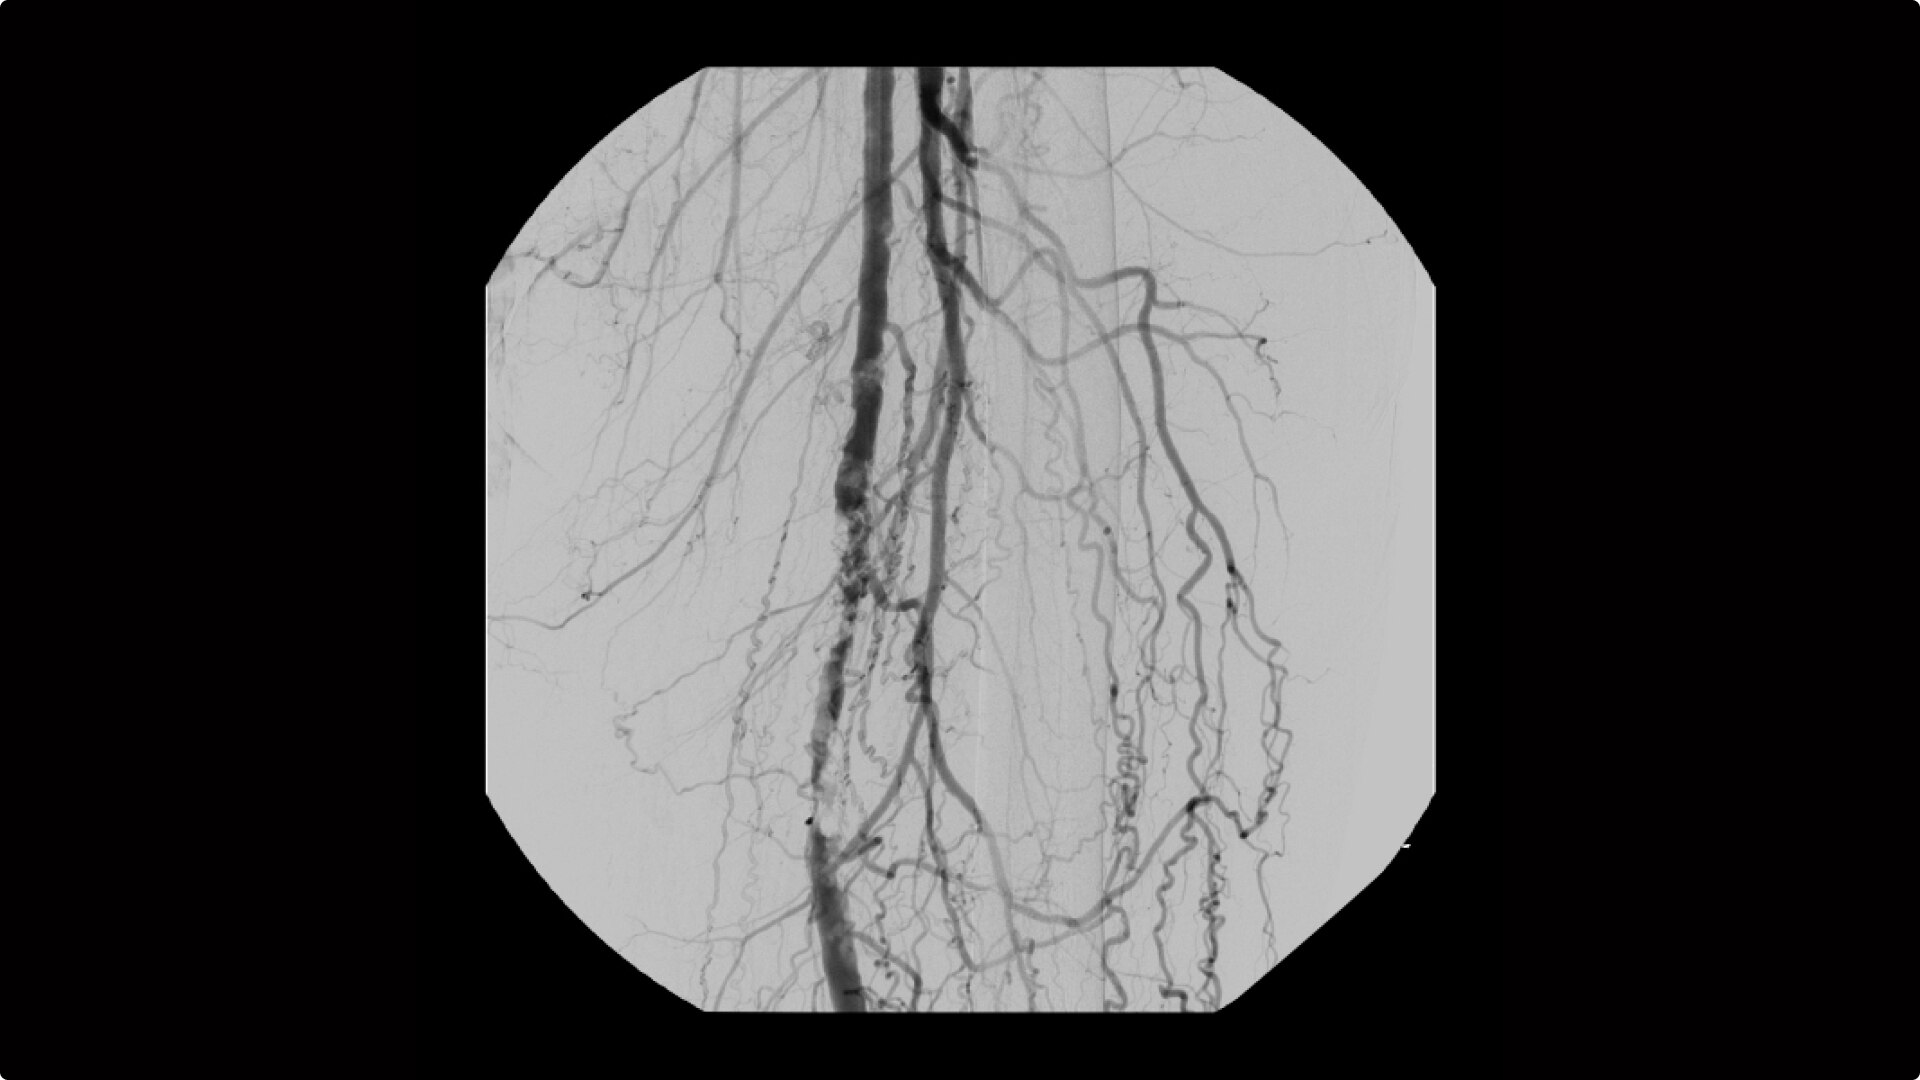

Perform a full leg Bolus Chase in one contrast run with a Preset Profile that includes Motion Tolerant Subtraction, that dynamically adjusts image quality based on presence of motion.

During contrast run-off procedures, easily select contrast type with positive (e.g. Iodine) or negative (e.g. Carbon Dioxide) during subtraction. The OEC Elite CFD cardiovascular package also includes Roadmapping.

OEC C-arms are used by interventionalists and surgeons to obtain vascular imaging during peripheral to contrast run-off procedures. Superb resolution, even in the presence of motion, enables easy identification of anatomical landmarks and the extremity of the catheter, even as catheter tip moves.

Clearly see 0.014” guidewires in chest and abdomen region or 0.008” guidewires in peripheral vascular with the OEC Elite CFD with a flat detector, image processing advancements and 4K viewing display.